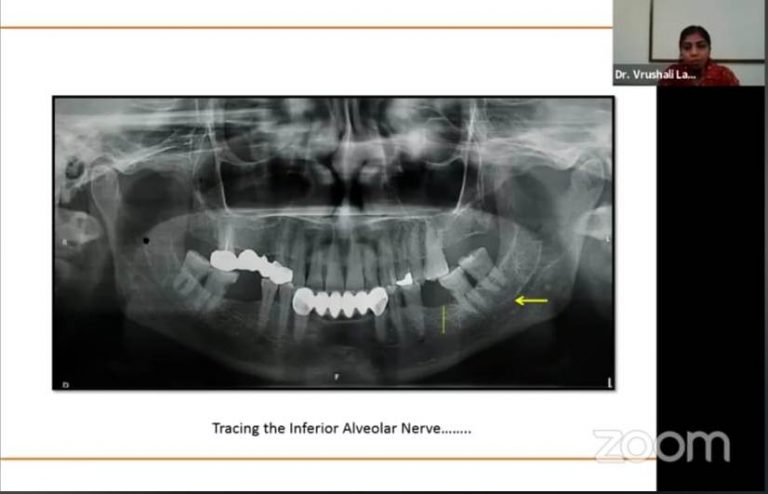

The Guest Speakers for the program on 26th February, 2021 were Dr Rajesh Gaikwad, DrVidya Baliga, Dr Vrushali Lathiya and Moderators were Dr Maya Indurkar, Dr Sangeeta Muglikar, Dr Swapna Mahale. Dr Rajesh Gaikwad conducted lecture on “Clinical diagnostic aids in periodontics” which was moderated by Dr Maya Indurkar, DrVidya Baliga conducted lecture on “Role of biomarkers in periodontal diagnostics” which was moderated by Dr Sangeeta Muglikar. Dr Vrushali Lathiya conducted lecture on “Diagnostic imaging in periodontal disease” which was moderated by Dr Swapna Mahale.